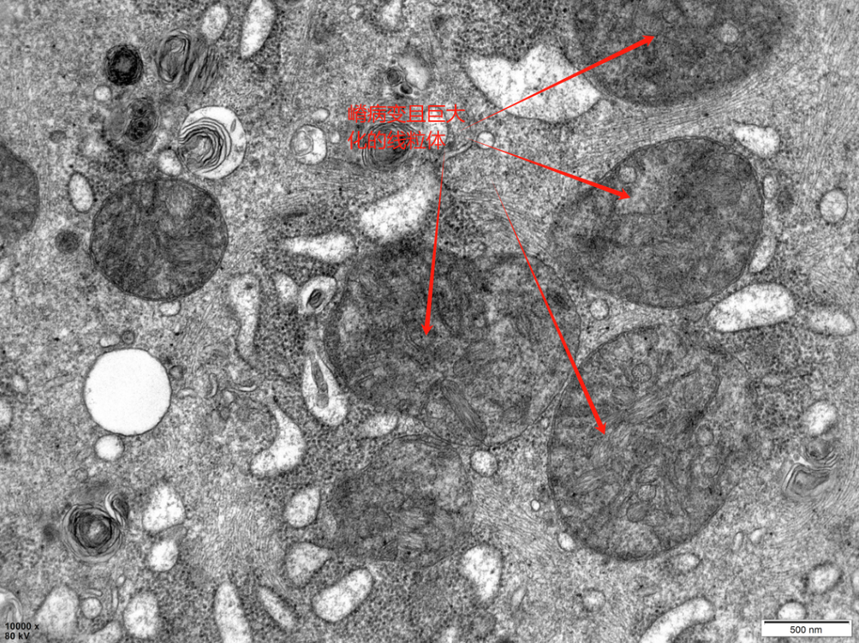

10000倍放大下,细胞线粒体超微结构

小鼠心肌组织中的线粒体 二、线粒体常见的超微结构病变: 1. 线粒体肿胀空泡化: • 基质肿胀:线粒体基质变稀,电子密度降低,嵴变短,数量减少,甚至消失。严重时,基质内形成多个电子透亮区,最终可能变成空泡状。 • 嵴内间隙肿胀:嵴内间隙(外室)扩张,导致线粒体外室肿胀,内室基质浓缩。 • 线粒体基质电子密度降低,形成空泡,基质颗粒消失,嵴结构变短,zui终可能成为不可逆的细胞坏死标志。